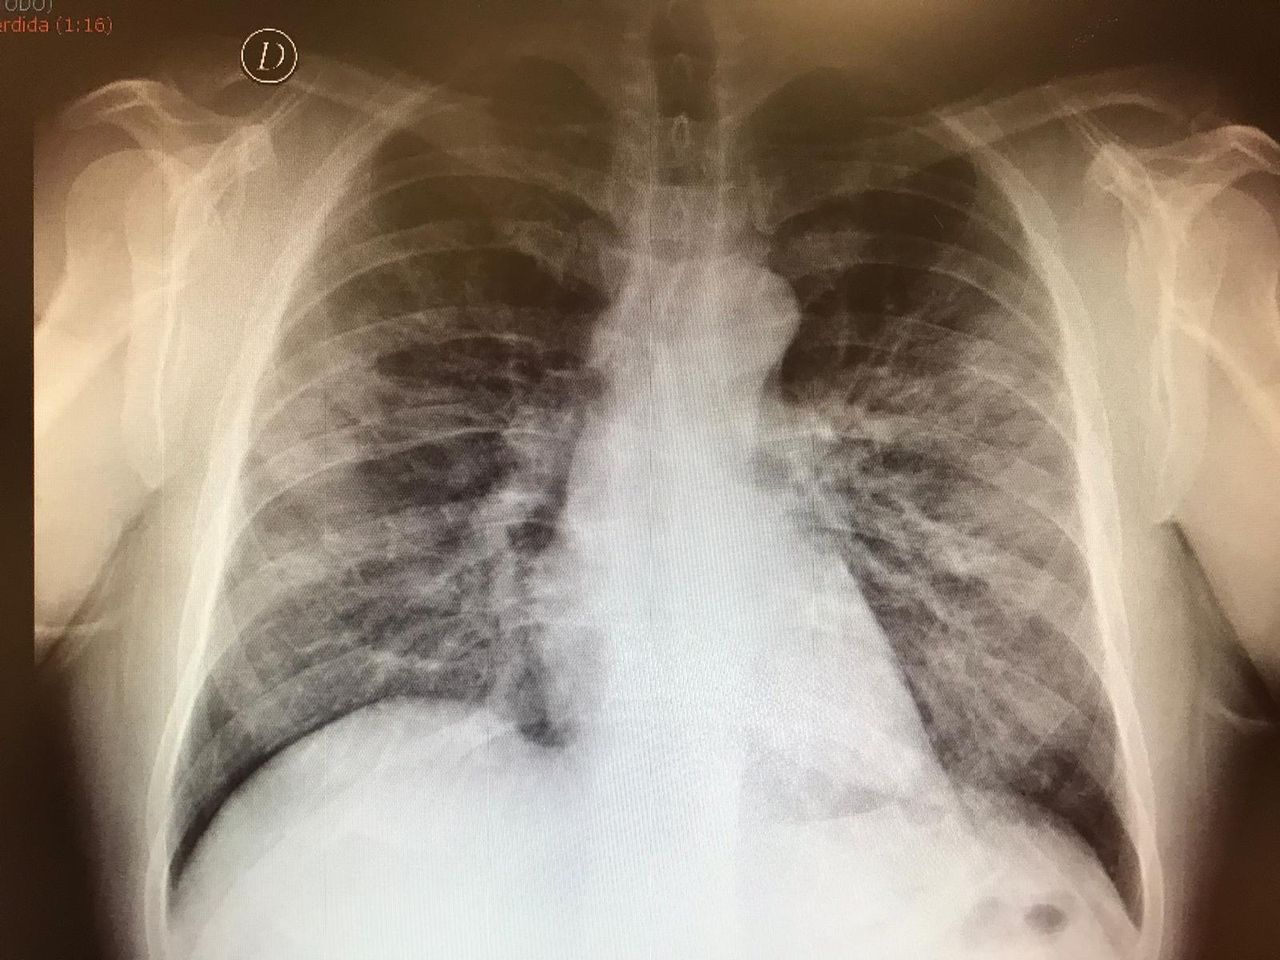

- DIAGNOSTICO PRECOZ DEL CANCER DE PULMON

- ECOGRAFIA PLEURAL Y PULMONAR